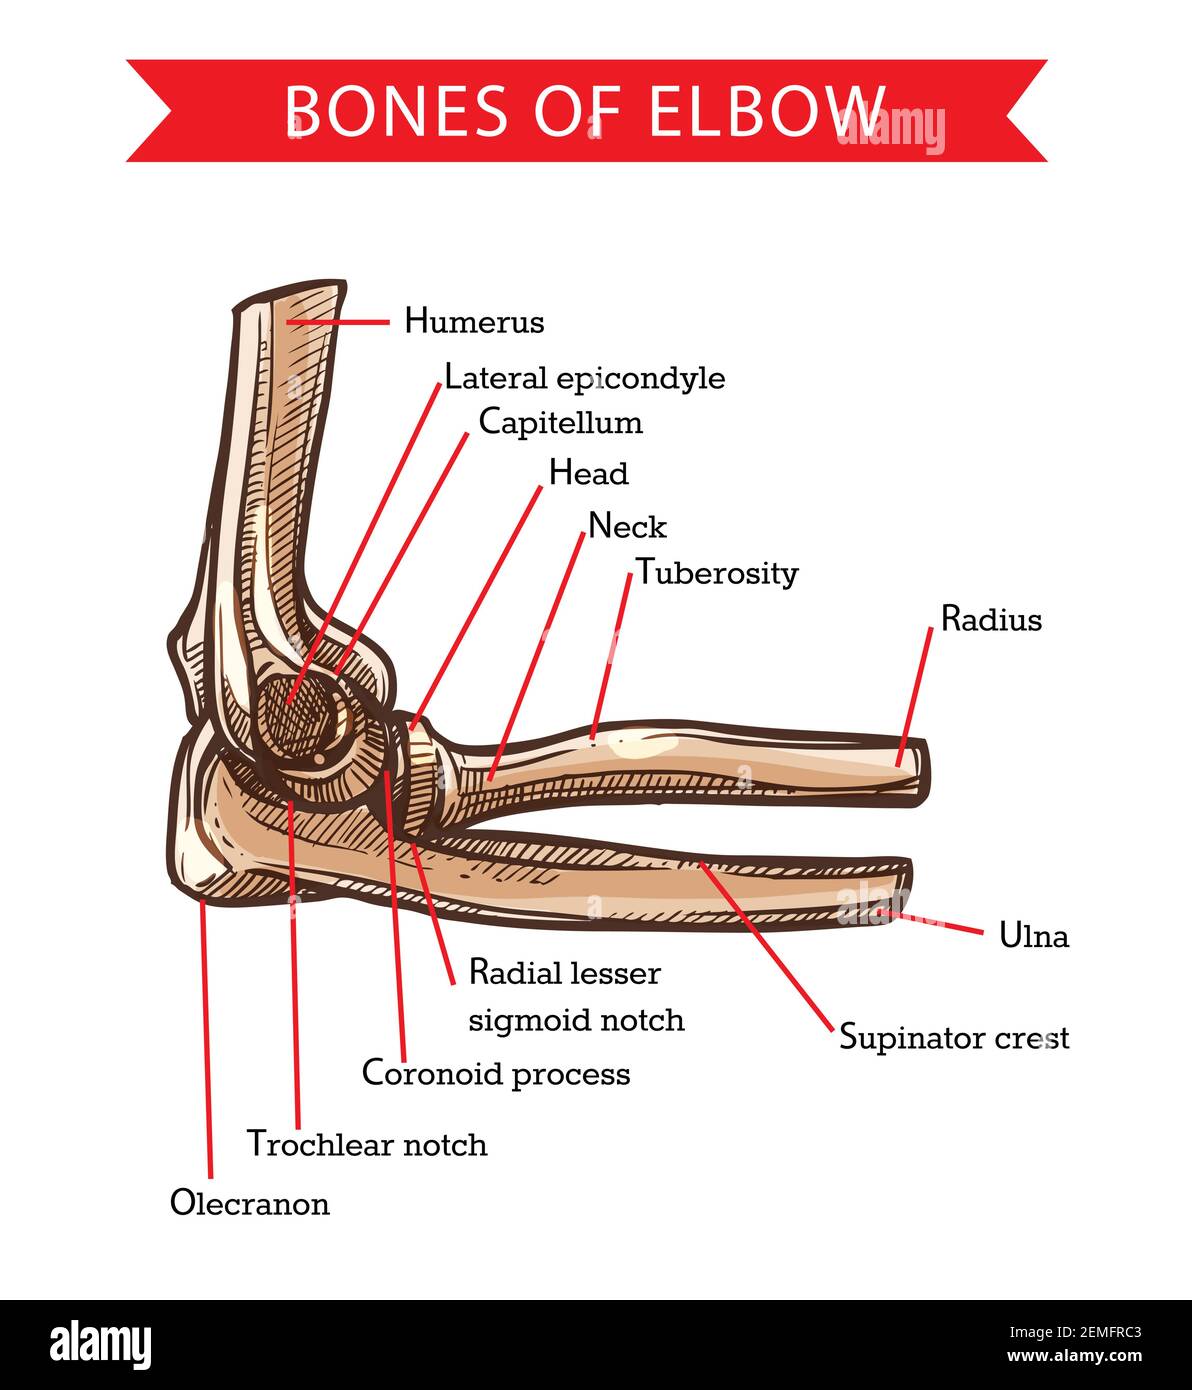

Elbow anatomy bones sale, Bones of elbow human anatomy vector sketch. Medicine and health care design with arm skeleton bones of humerus radius and ulna capitulum head nec Stock Vector Image Art Alamy sale

Bones of elbow human anatomy vector sketch. Medicine and health care design with arm skeleton bones of humerus radius and ulna capitulum head nec Stock Vector Image Art Alamy

Product Name: Elbow anatomy bones saleElbow Anatomy Dr Paul Jarrett Elbow Surgeon Perth sale, Elbow Joint Anatomy Function Common Conditions sale, Elbow Bones Names Basic Anatomy Diagrams sale, Elbow Joint What is it and common pains issues Brisbane Physiotherapy sale, Elbow Anatomy Problems Home Consultant Orthopaedic Surgeon sale, ELBOW ANATOMY INJURIES AND TREATMENT sale, Anatomy of the Elbow Southern California Orthopedic Institute sale, Elbow Anatomy New York NY sale, Tennis Elbow Definition Anatomy and Causes Jeffrey H. Berg M.D sale, Elbow Anatomy Revision Guide AnatomyStuff sale, Elbow Anatomy Main WikiSM Sports Medicine Wiki sale, Taoist Tai Chi Society Notes on Anatomy and Physiology The Elbow Forearm Complex sale, Basic Elbow Anatomy Joint Pain Info sale, Elbow Anatomy Elbow Pain Chicago Westchester Hinsdale IL Nikhil Verma MD sale, Osteoarthritis of the Elbow OrthoInfo AAOS sale, Illustration of the bony anatomy of the elbow Download Scientific Diagram sale, Elbow Cape Shoulder and Elbow Unit sale, Elbow Anatomy kentorthopaedicpractice sale, Elbow Fractures Brandon P. Donnelly MD sale, Bones of elbow human anatomy vector sketch. Medicine and health care design with arm skeleton bones of humerus radius and ulna capitulum head nec Stock Vector Image Art Alamy sale, Elbow Arm Anatomy sale, Elbow Anatomy Animated Tutorial sale, Elbow Anatomy Full Easy Review OrthoFixar 2025 sale, Elbow Joint Anatomy Movement Muscle involvement sale, The Elbow Joint Anatomy and 3D Illustrations sale, Elbow Replacement Kimball Health Services sale, Elbow Joint Anatomy video Lecturio Medical sale, Physical Therapy in Fremont Carbon and Sweetwater Counties for Elbow Anatomy sale, Bones of Elbow sale, The Elbow Joint Structure Movement TeachMeAnatomy sale, Elbow Joint Anatomy and Significance Bone and Spine sale, Elbow Olecranon Fractures OrthoInfo AAOS sale, Elbow joint Anatomy ligaments movements blood supply Kenhub sale, Anatomy of the Elbow sale, Poster Print Elbow joint anatomy infographic diagram bones humerus ulna radius parts structur 40x35.8 cm sale.